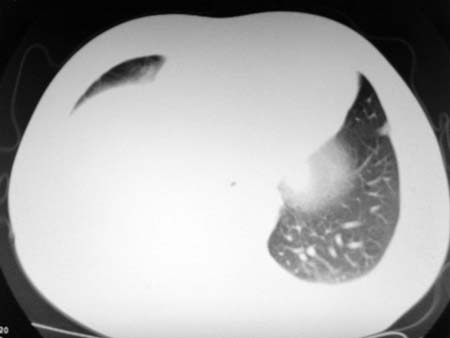

以下是引用qian在2008-4-27 17:02:00的发言:[br]考虑右下肺肺段隔离症伴有感染,建议做增强看看。

以下是引用zsl6918在2008-4-27 17:13:00的发言:[br]考虑右肺下叶炎性病变可能性大,建议抗炎治疗后复查,现有资料不能完全除外肺癌可能。